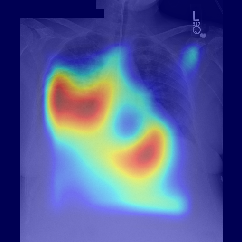

Fig.Β 5: Examples of class activation maps of positive cases. Left to right: image with annotation in blue, no L1 regularization, with L1 regularization, baseline.

Fig. 5 shows examples of class activation maps of positive cases for visual comparisons among the final models. These were produced using the Grad-CAM approach [14]. The images were annotated by an expert for the regions of opacity. Although all models correctly classified the cases as positives, the activation maps of the baseline model were barely correlated with the annotated regions, with more irrelevant hot spots outside the lungs. On the other hand, the activation maps of the models with feature selections were better correlated with the annotation. In other words, these smaller networks seems to be also more focused on the correct regions, which is a step towards explainability. The image in the third row shows that the VGG16 activation map has important components outside the lungs, focusing on English characters on the image. Whereas the reduced networks show more activation in marked areas of the lungs.